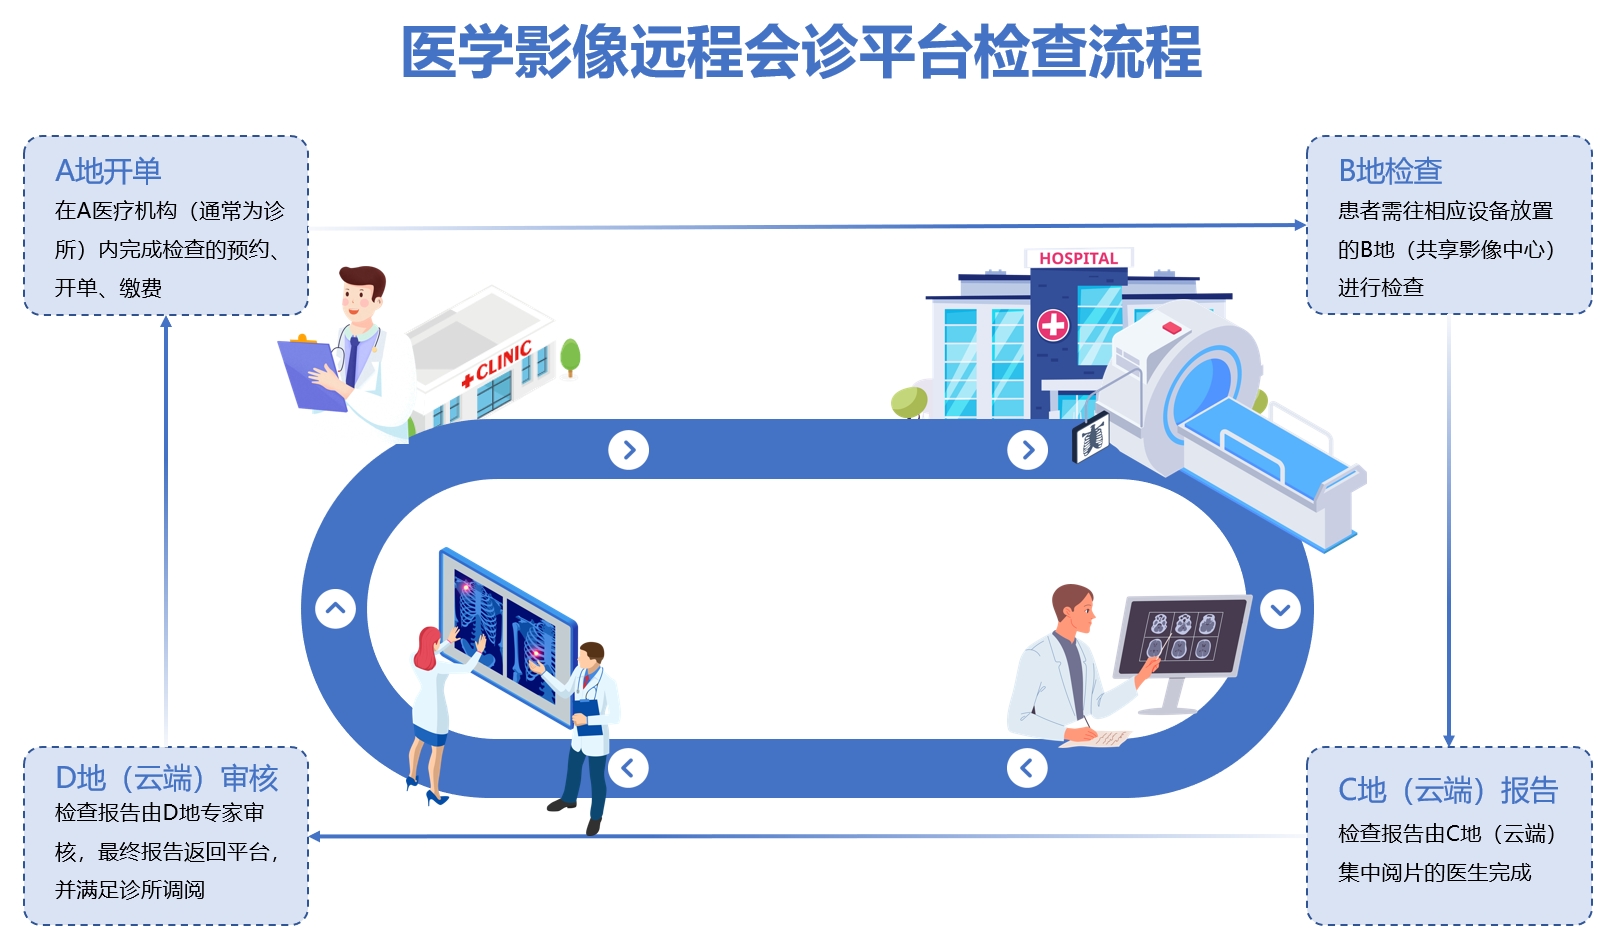

Remote

1111111